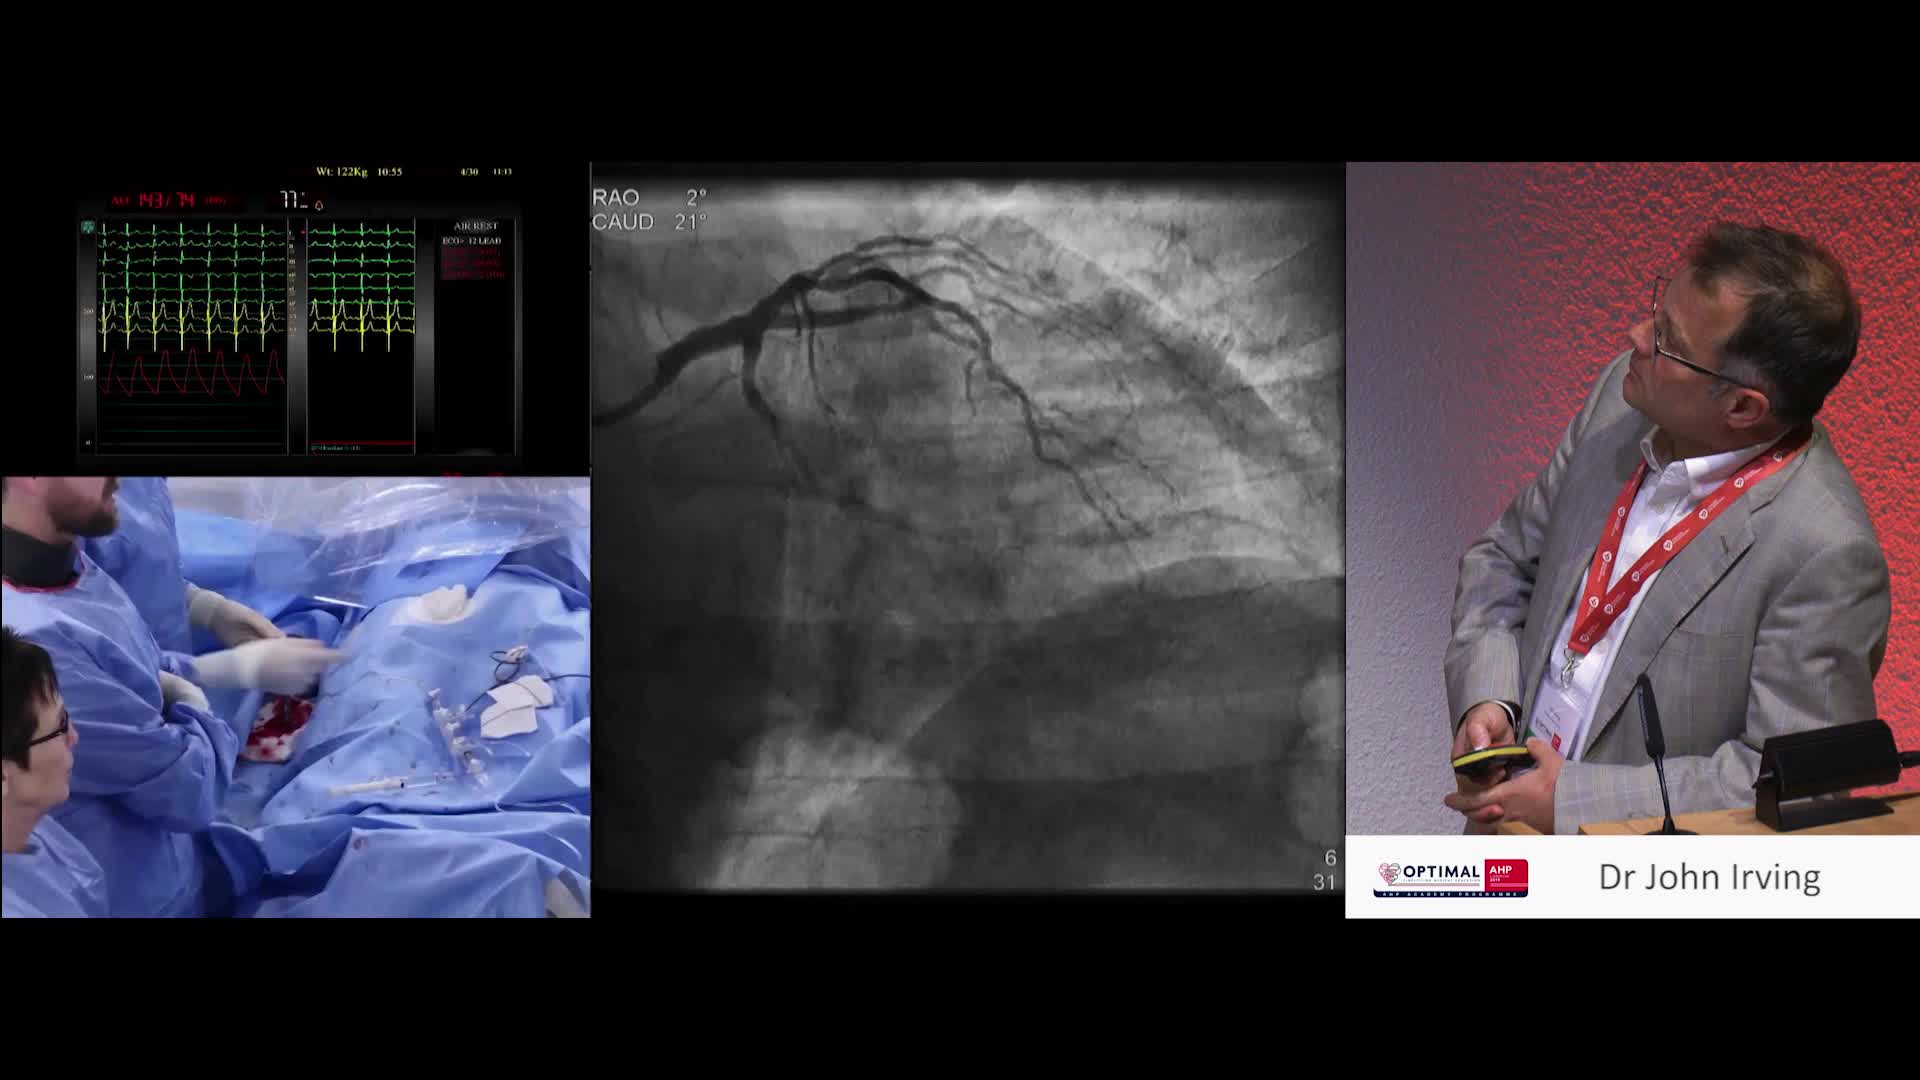

Live recorded case featuring FFR & iFR